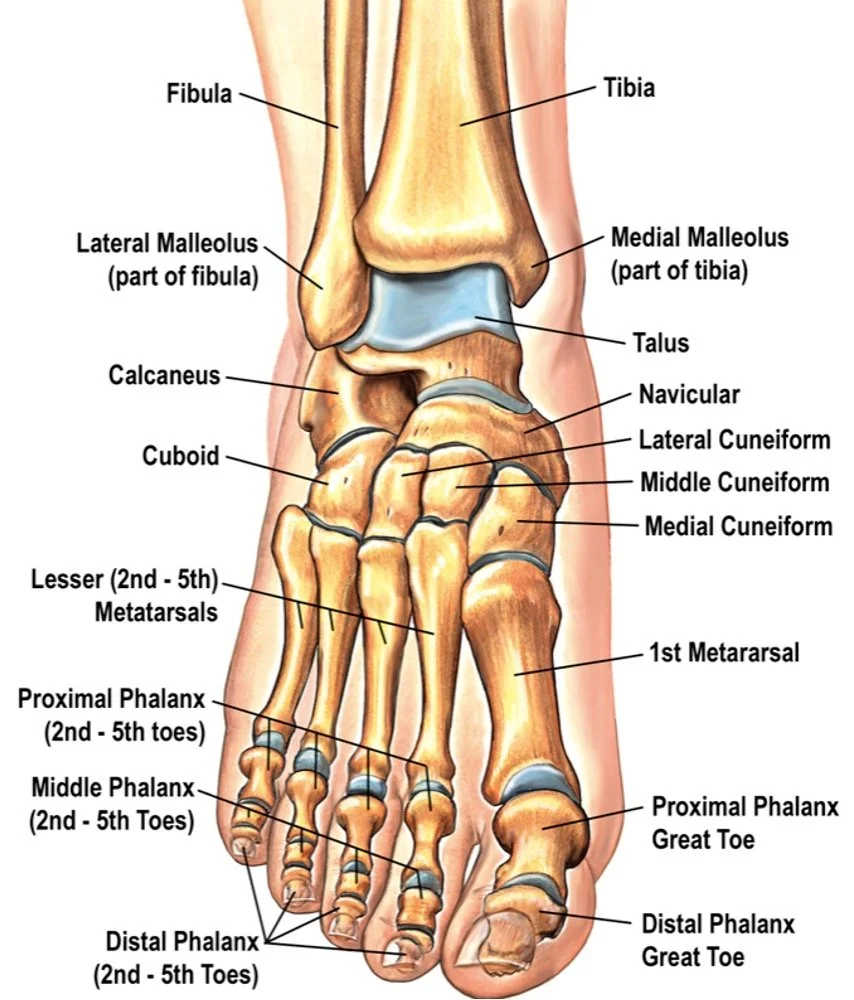

The human foot and ankle are composed of 26 bones and over 30 joints. Because of the complexity and the weight these structures bear, fractures vary significantly in severity. Use this guide to navigate specific injury types, classifications, and recovery expectations.

Ankle Fractures

• Lateral Malleolus: Fractures of the outer fibula.

• Medial Malleolus: Fractures of the inner tibia.

• Bimalleolar & Trimalleolar: Complex multi-bone injuries.

• Pilon Fractures: High-energy impact to the distal tibia.

Hindfoot Fractures

• Calcaneal (Heel) Fractures: Often caused by falls from height.

• Talar Fractures: Serious injuries affecting the "plug" of the ankle joint.

Midfoot Fractures

• Lisfranc Injuries: Critical injuries to the midfoot ligaments and bones.

• Navicular & Cuboid: Often related to stress or direct impact.

Forefoot Fractures

• Jones Fractures: A specific, high-risk break at the base of the 5th metatarsal.

• Metatarsal Stress Fractures: Common in runners and athletes.

• Toe (Phalangeal) Fractures: Breaks in the smaller bones of the toes.